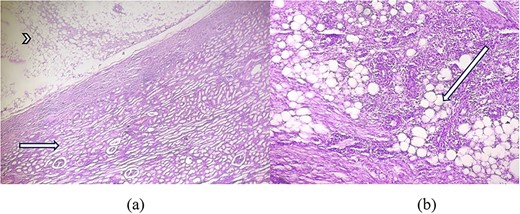

As shown in Fig. 3a, microscopic examination of H&E stained section showed tumour area consisting of adipose tissue and spindle cells with compressed renal parenchyma containing glomeruli and tubules. Another H&E stained section showed areas with mature fatty adipose tissue along with haphazardly arranged smooth muscle fibres having cigar shaped nuclei and fibrillary eosinophilic cytoplasm and many small vessels, infiltrated by dense mixed inflammatory cells consisting of lymphocytes and few plasma cellsas shown in Fig. 3b.

(a) H&E × 40 section shows tumour area (arrowhead) consisting of adipose tissue with compressed glomeruli and tubules (short arrow). (b) H&E × 100 section shows mature adipose tissue (long arrow) along with haphazardly arranged smooth muscle fibres and infiltrated by dense inflammatory cells.